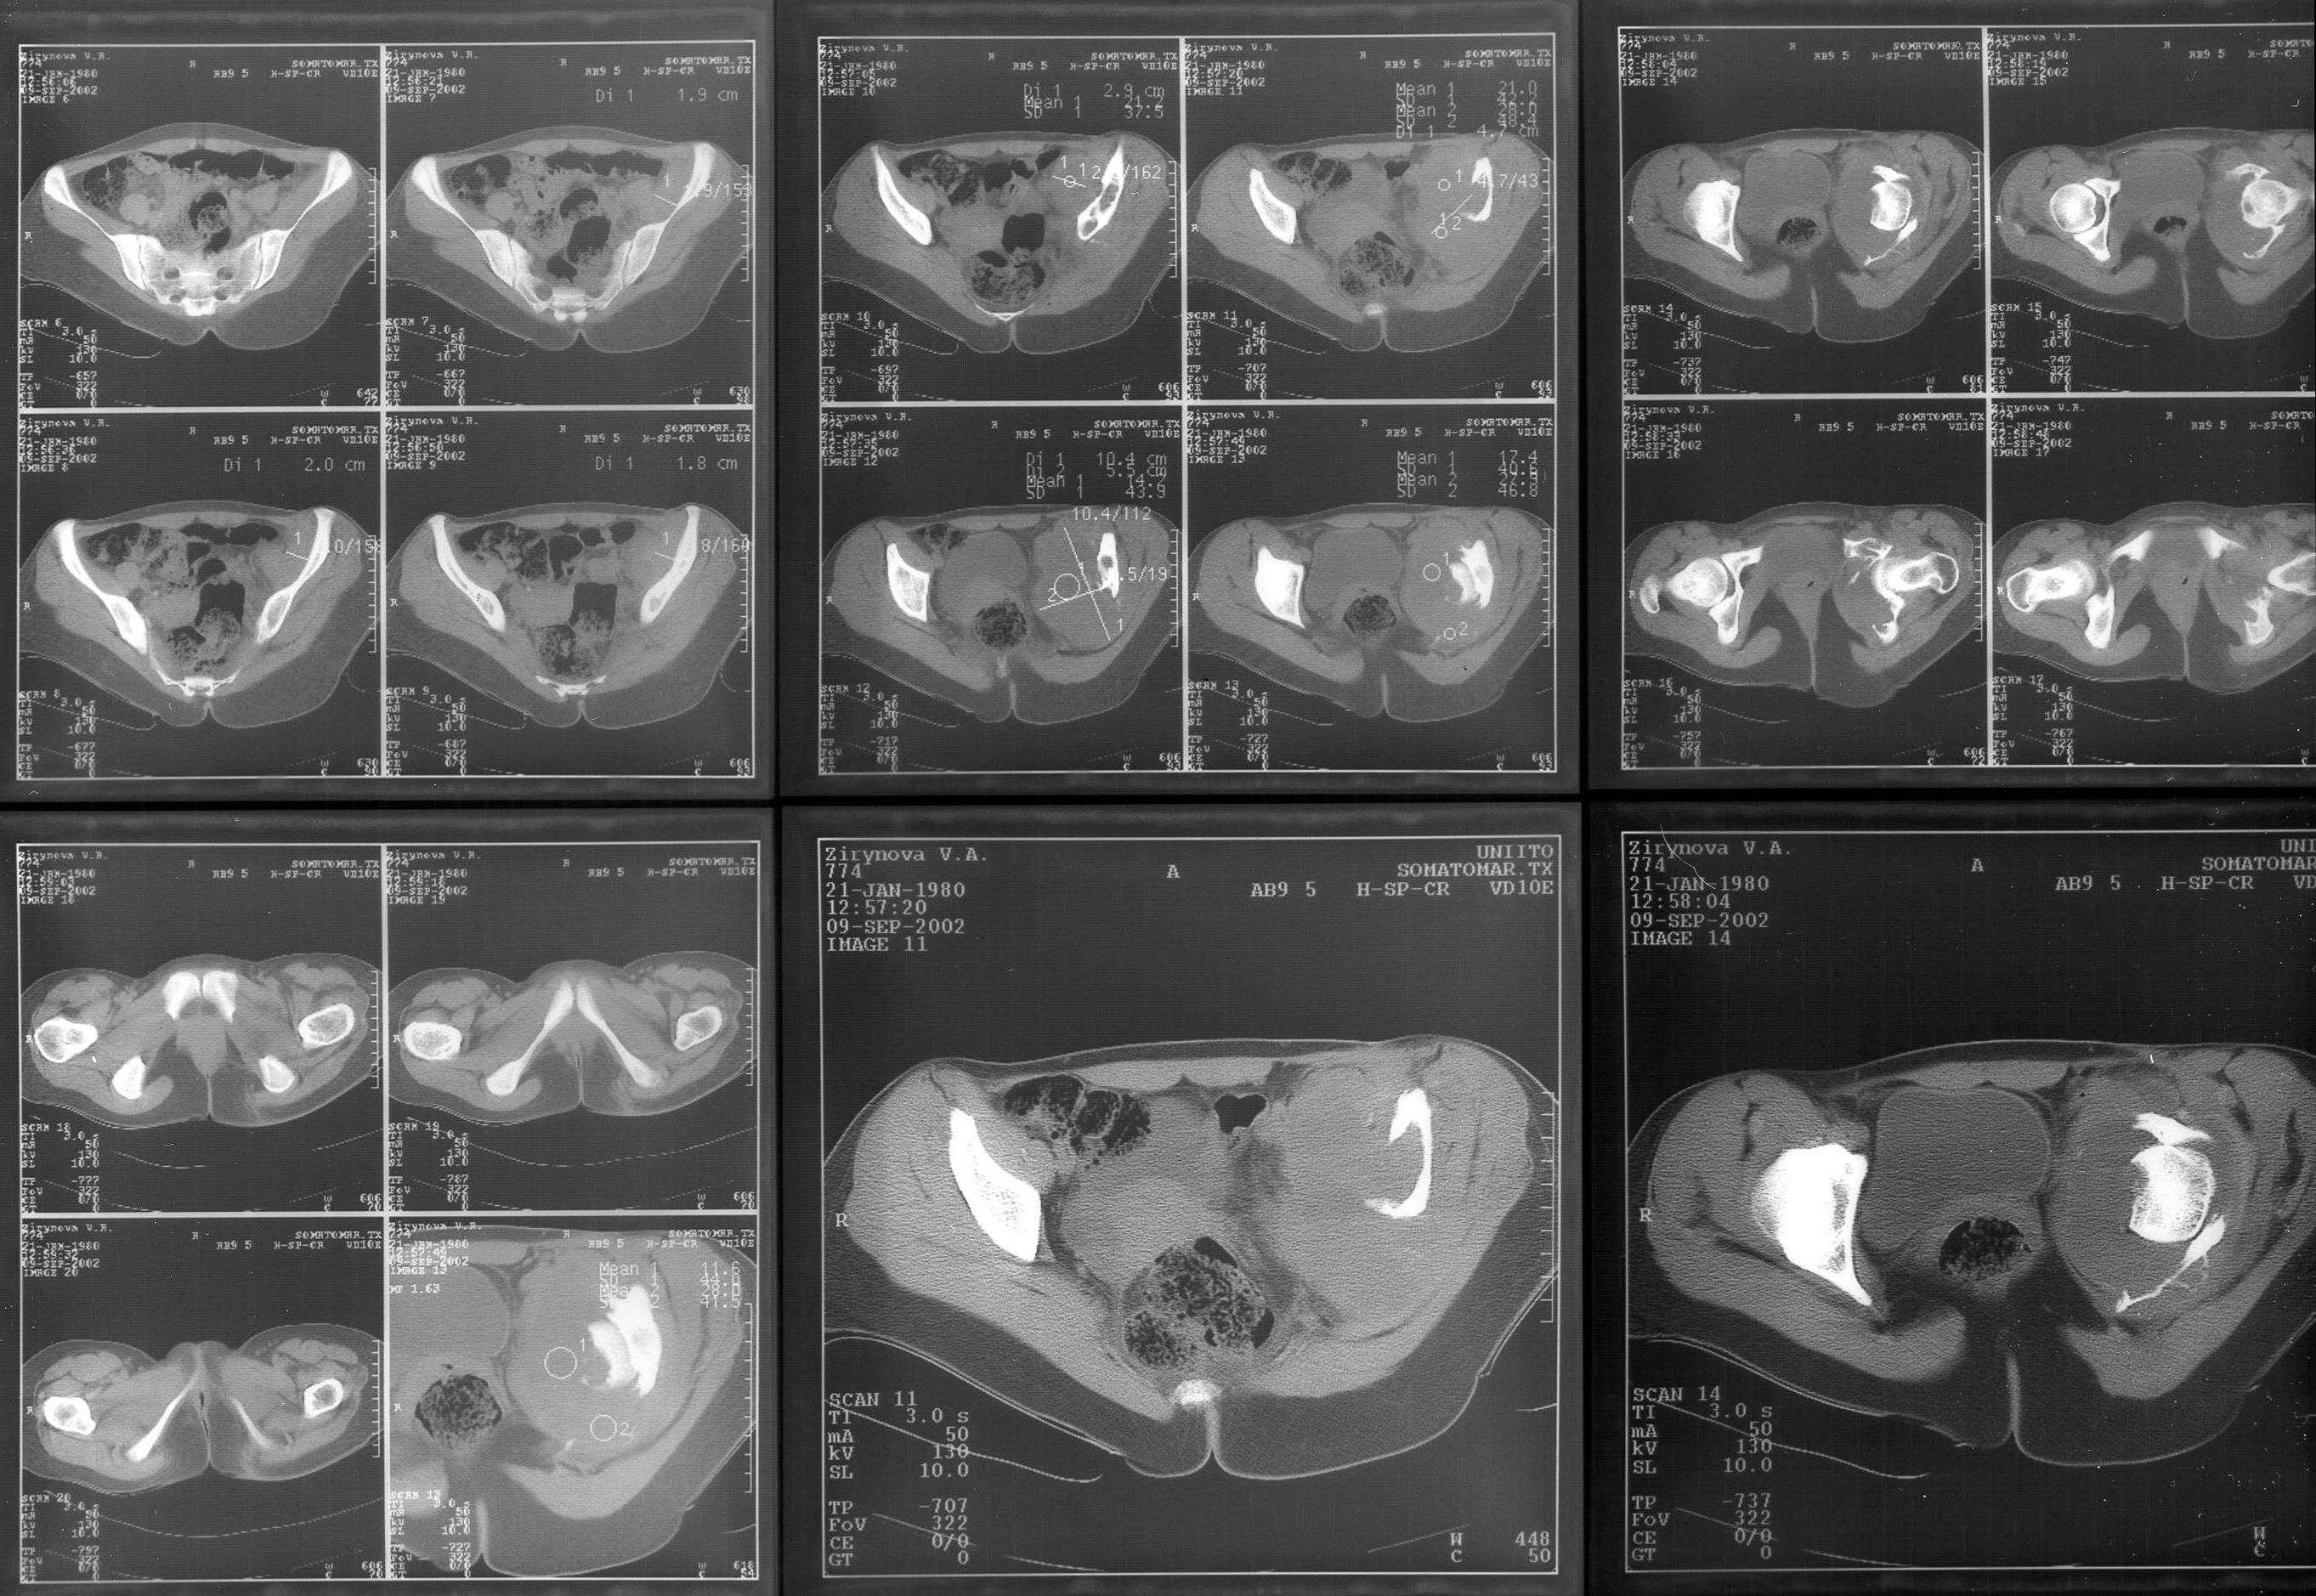

Женщина 22 лет поступила с протрузией вертлужной впадины.Рентгенограммы (1, 2) с интервалом в 1 год. В онкодиспансере сделали биопсию - ОБК без малигнизации. Какой объем операции здесь следует предпринять? Есть ли какие-то шансы на первичное эндопротезирование? Где такие операции делают? В том числе в Европе. Заранее спасибо.

The xray appearance is consistent with a bengin aggessive or malignant lesion involving both the acetablum and the femoral epiphysis (there appears to be erosions of the femoral head). The differential diagnosis would include non-tumor conditions such as Brown's tumor (a serum calcium should be measured), benign aggressive lesions such as GCT, ABC and chondroblastoma, and malignant lesions such as telangiectatic osteosarcoma and MFH of bone.

However, the extent of the tumor in the pelvis and lack of a cortical rim leading to a large uncontained defect would be too much bone loss for any type of acetabular reconstruction.

A wide resection with reconstruction with a saddle modular prosthesis would be an option depending on the status of the remainder of the ilium.

looking to the X-rays and CT scan it appears this young lady has an aggressive bone leasion.

I completely agree with Christian Veillete concerning differential diagnosis. There is necessary to perform biopsy to evaluate the tumor and its histological degree. Also should be done three dimensional CT scan and MRI to evaluate the precise lack of the bone tissue and involvement of surrounding tissues.

The X-ray and CT scan appearance is likely as the chondrosarcoma what is seldom but common

finding in the replacement surgery of the hip. Having precise histological, CT and MRI data should be planed the amount of surgery after detailed discussion with patient. There is no any possibility to perform primary replacement. If there is the chondrosarcoma hemipelvectomy would be the most live saving procedure. If there is an aggressive giant cell tumor or other findings about allografting, reconstructive surgery with custom made implant or saddle modular prostheses (W.Link) could be discussed. In other wards there are so many different thinks what should be discussed with patient